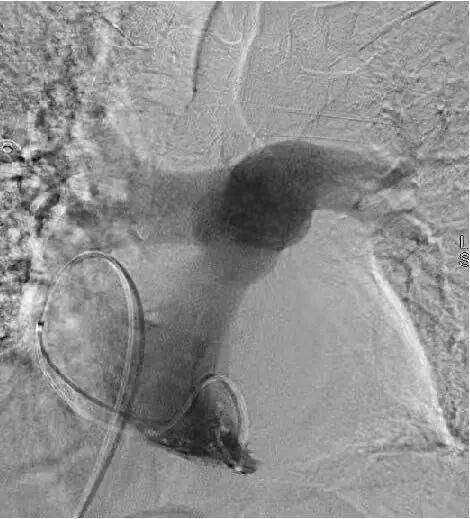

首先通过下肢静脉造影,清晰定位血栓位置与负荷;

最后通过肺动脉造影,精准实施取栓、碎栓操作。